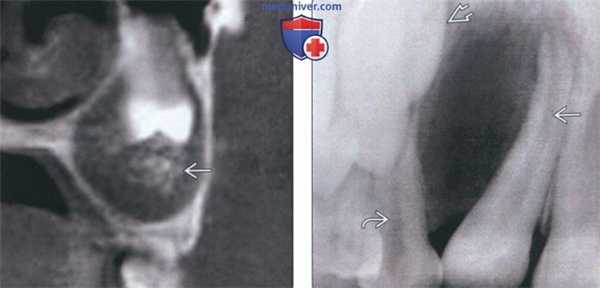

(Слева) На корональной КЛКТ определяется АОО, окружающая коронку и корональную треть корня второго премоляра верхней челюсти слева со смещением его в верхнечелюстную пазуху. Возле коронки зуба визуализируются кальцинаты.

(Справа) На периапикальной рентгенограмме определяется полностью рентгенонегативная АОО между корнями смещенного постоянного бокового резца верхней челюсти и временного клыка. Формирующийся постоянный клык отклонен.